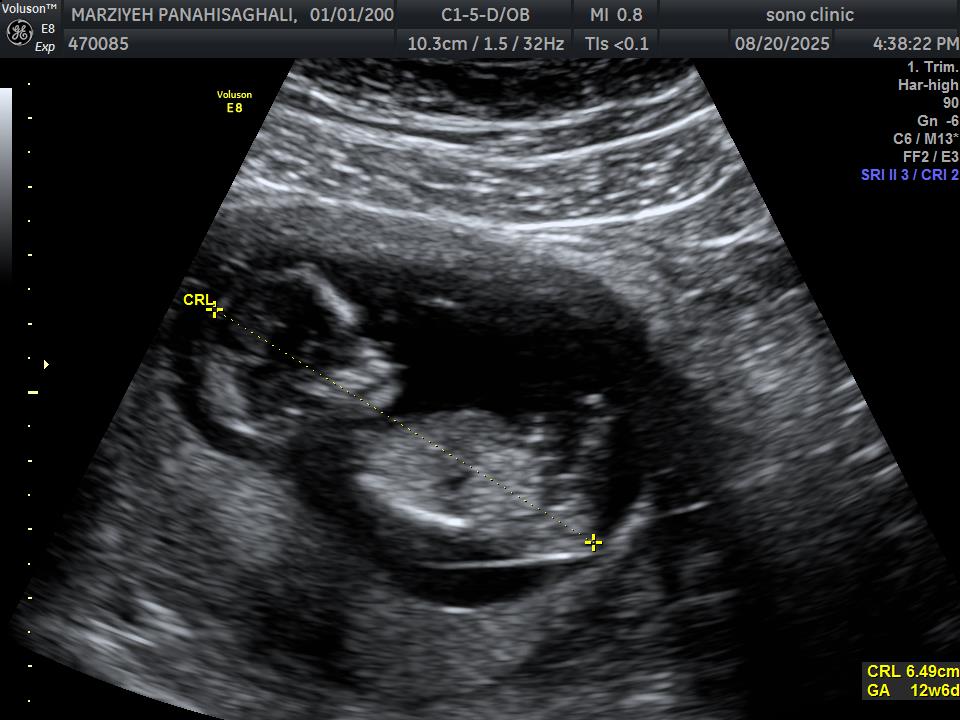

marzi81p مدیر استارتر عضویت: 1404/06/08 تعداد پست: 0 عنوان نی نی من 15 بازدید | 0 پست میتونید بگید نی نی من چیه دخملی یا پسر? 1404/06/08 | 21:44 0 نفر لایک کرده اند ... گزارش تاپیک نامناسب